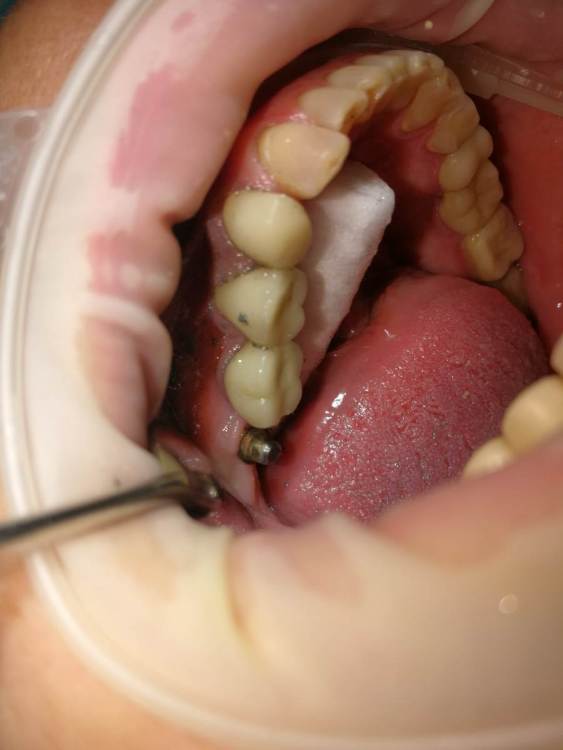

Turalyon Опубликовано 24 декабря, 2021 Поделиться Опубликовано 24 декабря, 2021 Приветствую, коллеги. У пациентки лет 10 назад установлены предположительно импланты Straumann, планируется замена коронок. Под старой коронкой вот такой мультиюнит, не знаю чем открутить. В каталоге подходящих ключей не нашел. 1) каким ключом можно попробовать открутить? диаметр около 3 мм 2)Что, если не откручивая снять оттиск с уже установленных мультиюнитов для изготовления новых коронок? Ссылка на комментарий

kramer Опубликовано 24 декабря, 2021 Поделиться Опубликовано 24 декабря, 2021 Это не мультиюнит, а монолитный абатмент. Откручивается специальным ключом. Или снимать оттиск с уровня абатмента 1 Ссылка на комментарий